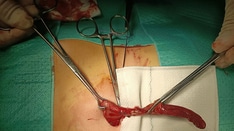

-

Ogilvie syndrome.